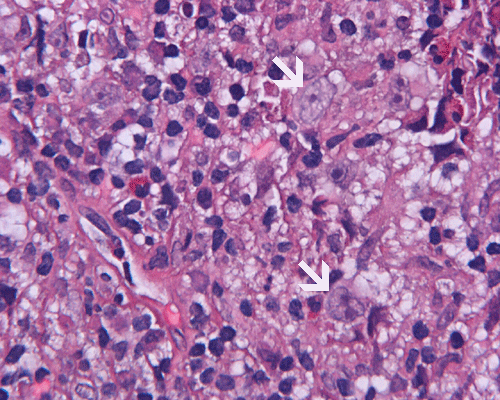

Paraffin sections: The entire volume of the tissue is made up of a granulomatous inflammation with poorly formed granuloma (Panel F, G, and H). The density of the lymphocytes is variable in different areas. In some areas, there is a rather intense lymphocytic infiltration accompanied by scant atypical cells with enlarged nulcei and prominent nucleoli (arrows in Panel I and J, Panel J is a higher magnification of Panel I). These atypical cells are quite easy to be missed. No microorganisms were identified by acid fast stain, PAS stain or GMS stain. The lymphocytes but not the atypical cells are positive for CD20 (Panel K) or CD3 (Panel L). The granulomatous background is strongly positive for CD68 (Panel M). Only rather faint positive staining for placental alkaline phosphatase (PLAP) is demonstrated and the interpretation is difficult as they are present in areas with crush artifact (Panel N). Many of the large, atypical cells are positive for CD117 (c-kit) (Panel O).

Intracranial germinoma is histologically identical to ovarian dysgerminoma and testicular seminoma. There is a tendency to infiltrate adjacent structures and to spread throughout the ependyma, the ventricular system and subarachnoid spaces. Microscopically, they consist of nests, lobules, cords, and/or sheets of large round tumor cells with well-defined borders, clear to pale cytoplasm with artifactual vacuolization, round and centrally located nuclei with open chromatin and prominent round or bar-shaped nucleoli. The cytoplasm is glycogen-rich, making these cells periodic acid-Schiff (PAS)–positive and diastase sensitive. These tumor cells are mitotically active. Atypical mitosis, however, is not a common finding. Necrosis is usually not prominent.  In the most classic histologic picture, clusters and cords of large germinoma cells are separated by a dense, lymphocytic infiltration admixed with some macrophages and a delicate fibrovascular network. Plasma cells may be found. At medium-power magnification with hematoxylin and eosin stain, the contrast between the smaller, darkly staining lymphocytes and the larger, pale staining cytoplasm of neoplastic cells is virtually pathognomonic. The amount of inflammatory cells can have wide variations among different tumors. In some occasions, the large germinoma cells are difficult to be found and the overall picture may suggest a lymphoma. Syncytiotrophoblastic cells can also be present. These cells should not be mistaken as evidence of choriocarcarcinoma.

Granulomatous changes are common findings in germinomas and intracranial germinomas follow this general trend 3, 4, 5. It can be extensive. This feature is particularly problematic in neuropathologic when stereotactic biopsy is performed and the amount of tissue available for examination is limited as illustrated in this case. During intraoperative consultations, a frozen section diagnosis of granulomatous inflammation should prompt additional sampling as isolated granulomatous inflammation of infectious origin and sarcodosis are quite uncommon in the pineal gland.